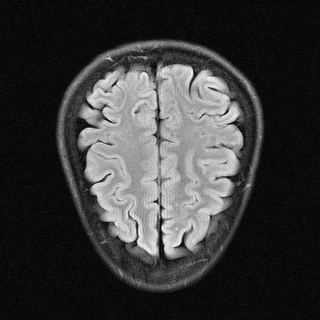

This article presents a novel undersampled magnetic resonance imaging (MRI) technique that leverages the concept of Neural Radiance Field (NeRF). With radial undersampling, the corresponding imaging problem can be reformulated into an image modeling task from sparse-view rendered data; therefore, a high dimensional MR image is obtainable from undersampled $k$-space data by taking advantage of implicit neural representation. A multi-layer perceptron, which is designed to output an image intensity from a spatial coordinate, learns the MR physics-driven rendering relation between given measurement data and desired image. Effective undersampling strategies for high-quality neural representation are investigated. The proposed method serves two benefits: (i) The learning is based fully on single undersampled $k$-space data, not a bunch of measured data and target image sets. It can be used potentially for diagnostic MR imaging, such as fetal MRI, where data acquisition is relatively rare or limited against diversity of clinical images while undersampled reconstruction is highly demanded. (ii) A reconstructed MR image is a scan-specific representation highly adaptive to the given $k$-space measurement. Numerous experiments validate the feasibility and capability of the proposed approach.